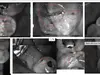

* digitālos zobu rentgenuzņēmumus (BW),

* administrācija korekti informēja, ka iespējams nosūtīt **BW rentgenu attēlu ekrānuzņēmumus**,

* savukārt **pilna apjoma diagnostikas dati (piemēram, intraorālās skenēšanas faili un rentgenu oriģinālfaili)** ir pieejami specializētā medicīniskā programmatūrā un to izmantošanai nepieciešama atbilstoša programmatūra un formāts.